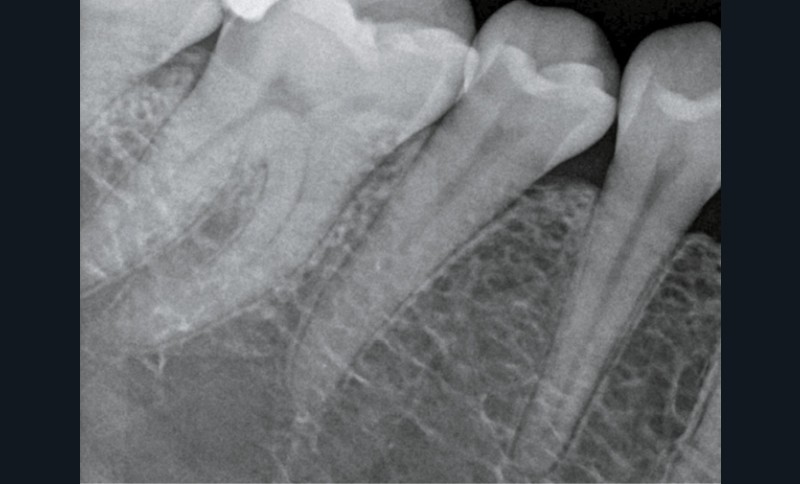

Dans son exercice quotidien, l’omnipraticien est souvent confronté à la réalisation de restaurations impliquant la gestion de marges sous-gingivales. Les causes sont multiples : fracture, lésions carieuses profondes (le plus souvent en proximal), résorptions externes…

- lors de la réalisation du soin : accès rendu difficile, saignement, perte d’étanchéité, isolation complexe avec le seul champ opératoire et les limites de la préparation ne seront pas – ou peu – accessibles lors de la prise d’empreinte, en technique conventionnelle ou par empreinte optique ;

Lors d’atteinte sous-gingivale profonde, la restauration se retrouve en regard d’une zone charnière du parodonte qu’est l’attache supra-crestale ou « espace biologique » (fig. 1) [5, 6]. Cette attache gingivale s’insère le long de la racine dentaire, allant de la partie la plus coronaire de l’attache épithéliale à la partie la plus apicale de l’attache conjonctive. Elle mesure en moyenne 2,04 mm chez le sujet sain, comprenant 0,97 mm d’attache épithéliale et 1,07 mm d’attache conjonctive. Au-dessus, le sulcus est de 0,5 mm.

Il est admis que si l’attache parodontale n’est pas préservée lors d’une procédure restauratrice, une inflammation gingivale, une perte d’attache et une résorption osseuse incontrôlée se développent. Cliniquement, ces changements se manifestent par des poches parodontales et des récessions gingivales.